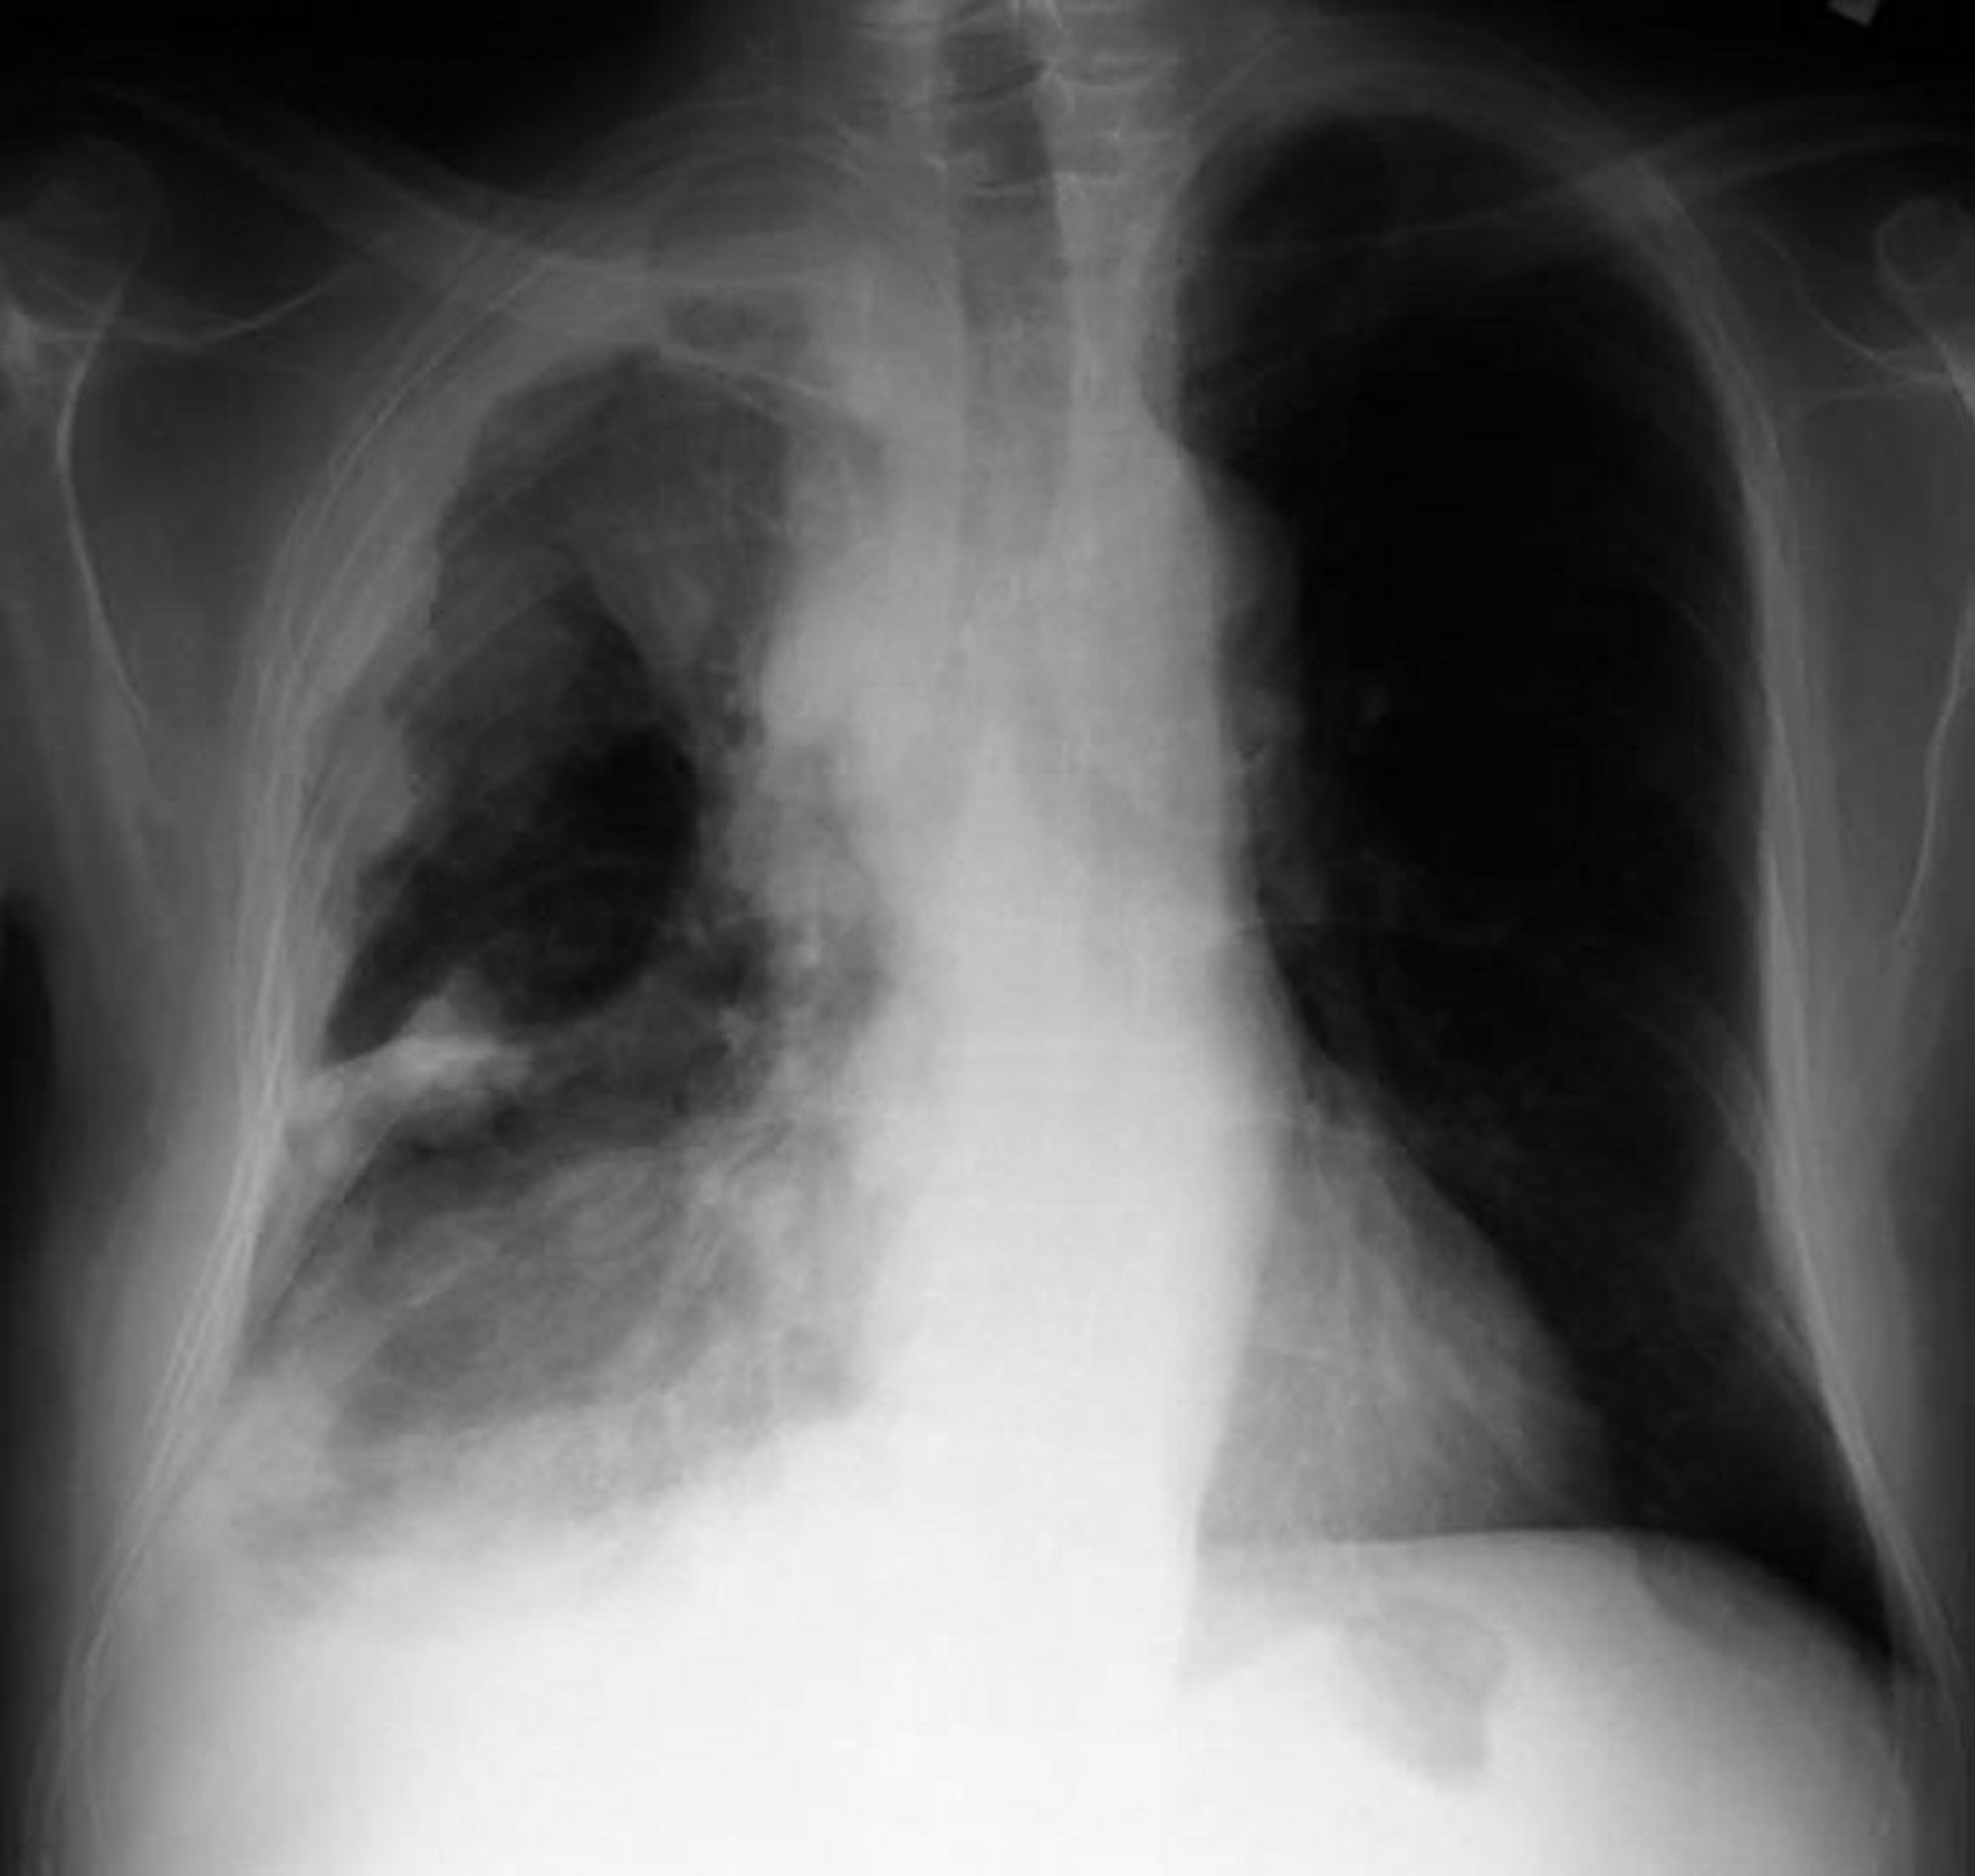

Mesotelioma pleural

Radiografia de tórax de um paciente com mesotelioma pleural mostra espessamento pleural com massas nodulares na pleura parietal.

By permission of the publisher. From Huggins J, Sahn S. In Bone's Atlas of Pulmonary and Critical Care Medicine. Edited by J Crapo. Philadelphia, Current Medicine, 2005.